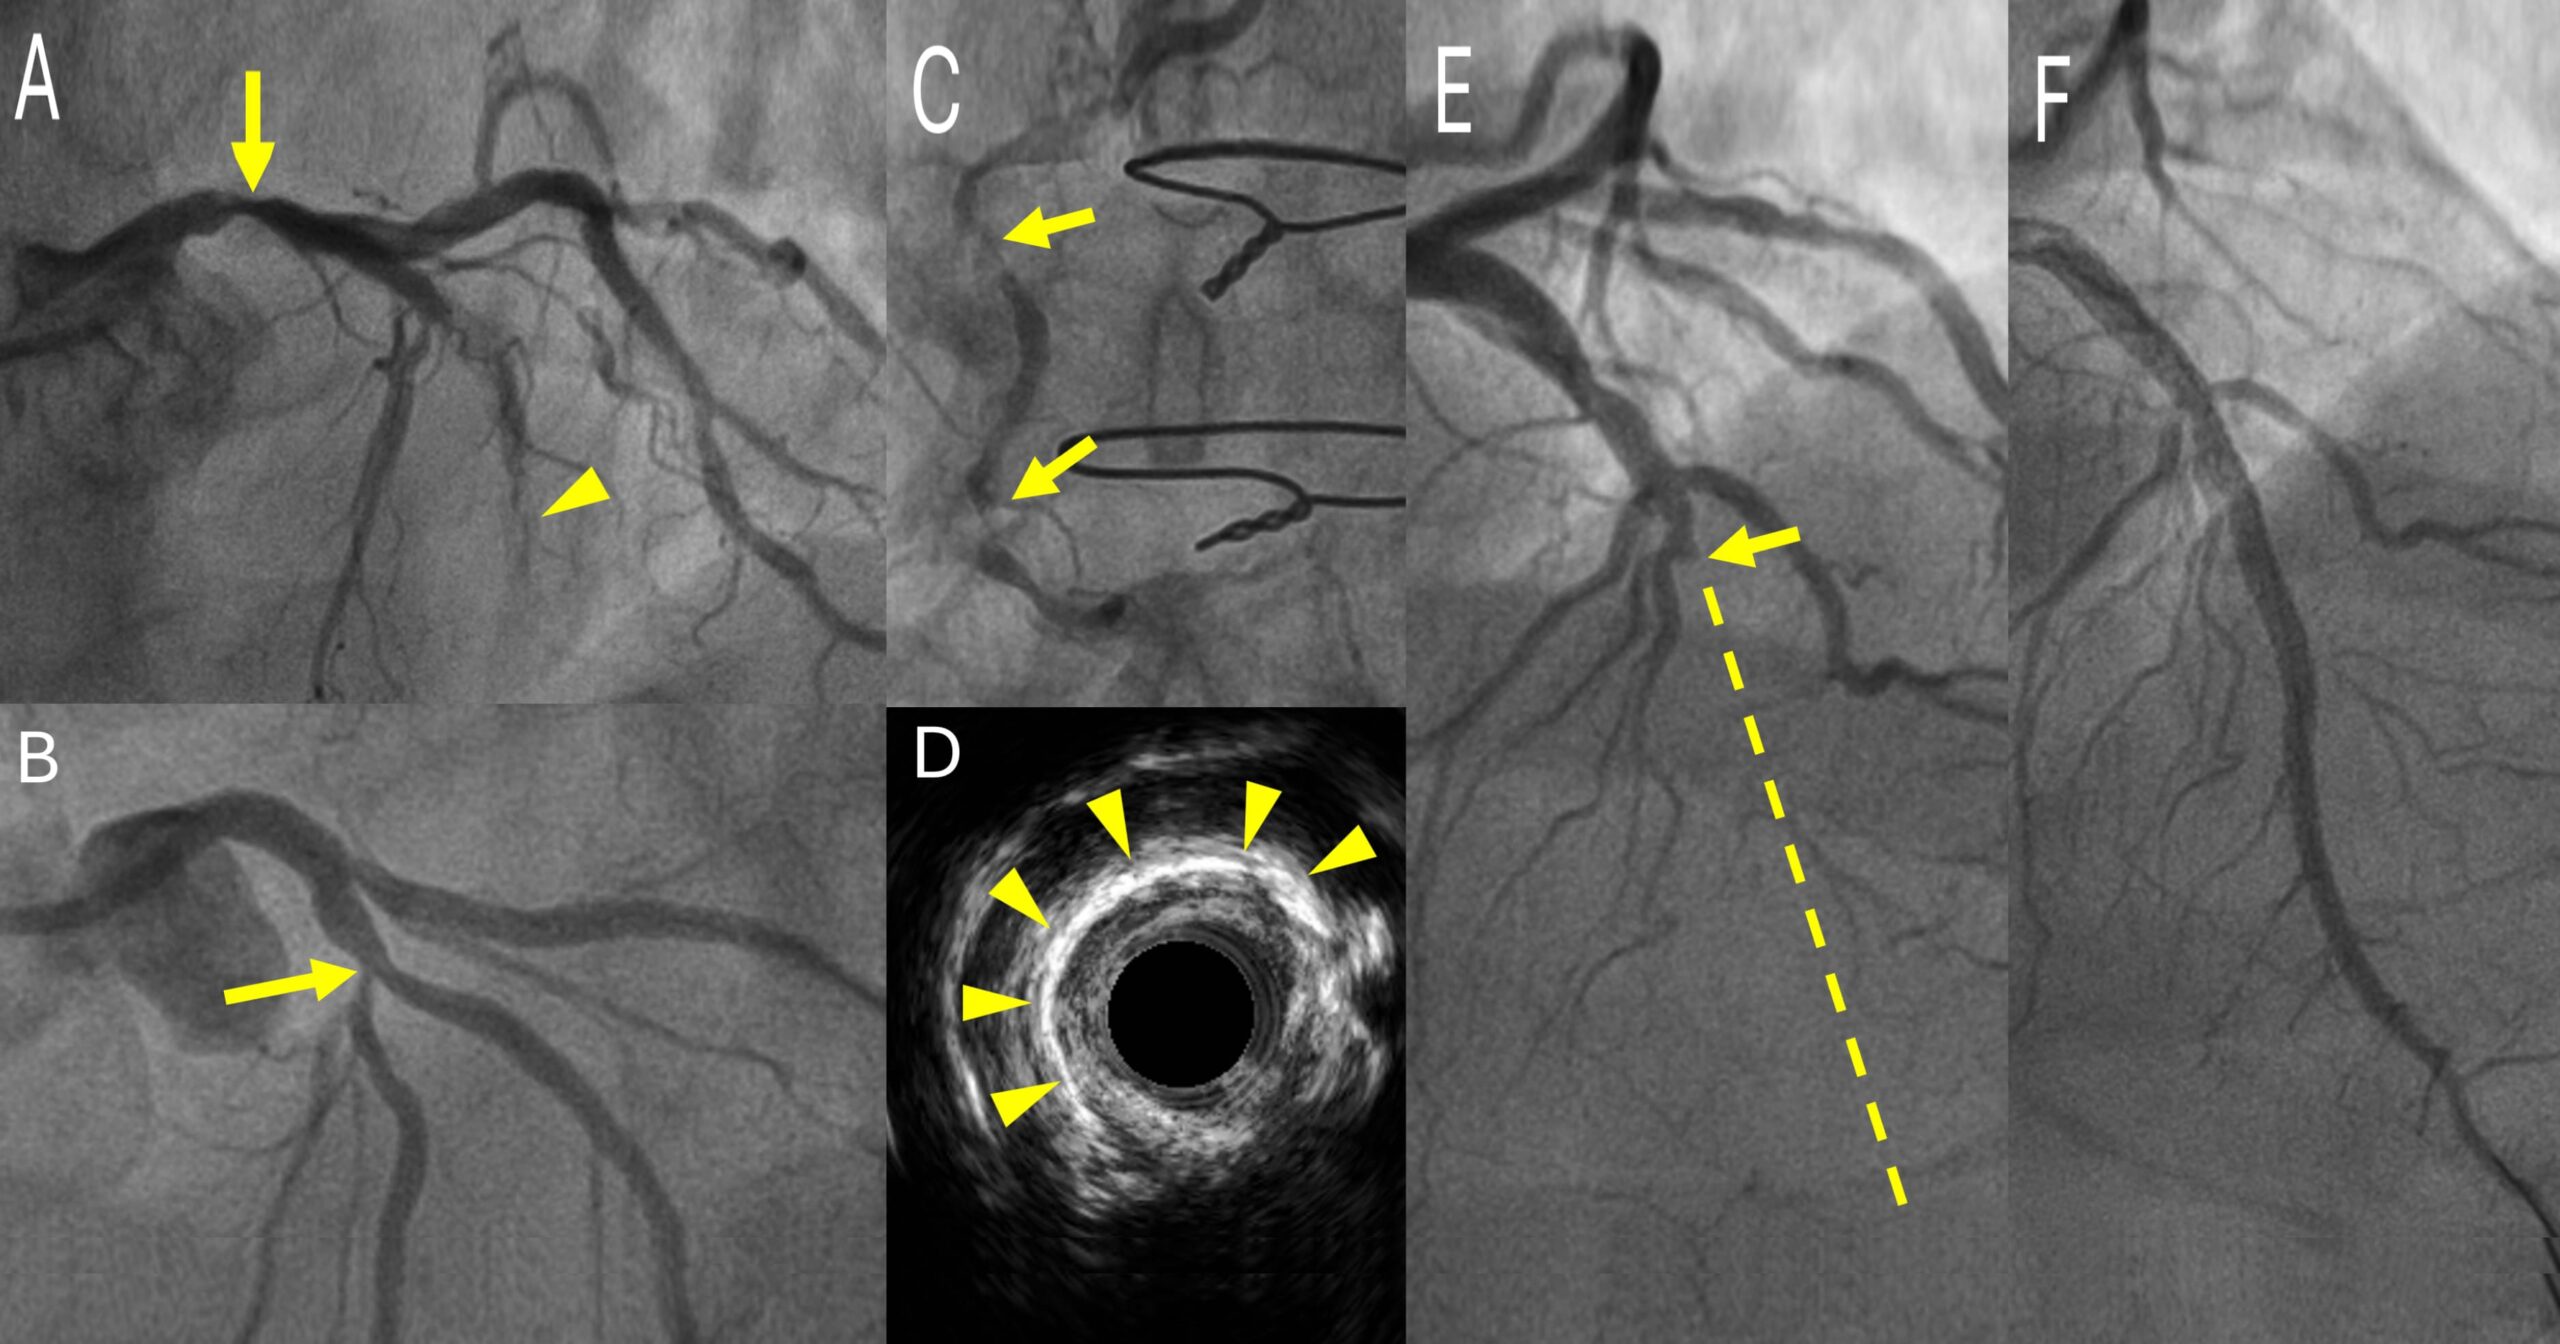

- รอยตีบที่หลอดเลือดต้นขั้ว (Left Main) (ลูกศร) และการอุดตันในขดลวด (หัวลูกศร)

- รอยตีบที่ทางแยกหลอดเลือด (Bifurcation Lesion)

- รอยตีบที่มีหินปูนเกาะ (Calcified Lesion)

- ภาพ Intravascular Ultrasound แสดงตำแหน่งและปริมาณของหินปูนที่เกาะในหลอดเลือด (หัวลูกศร)

- หลอดเลือดตันเรื้อรัง (Chronic Total Occlusion) ลูกศรแสดงจุดที่ตัน เส้นประแสดงแนวของหลอดเลือดที่ควรจะเป็น

- รอยโรคอุดตันในภาพ E หลังเปิดหลอดเลือดได้สำเร็จ